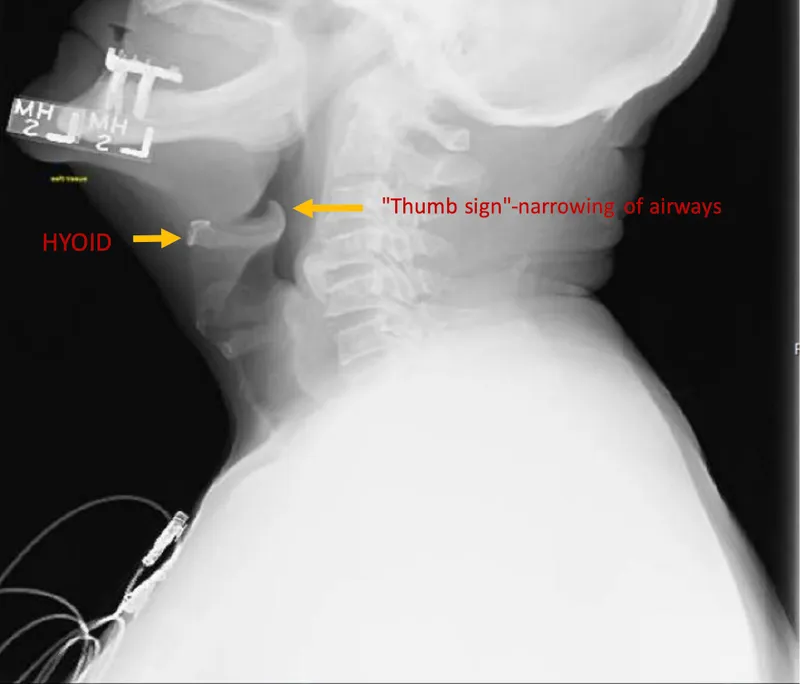

Croup vs. Acute Epiglottitis:

Feature Croup (LTB) Acute Epiglottitis Etiology Parainfluenza virus Haemophilus influenzae type b (Hib) Onset Gradual Rapid Cough Barking Muffled/Absent Drooling Absent Present Fever Low-grade High Posture Any Tripod X-ray Sign Steeple sign Thumb sign

📌 Epiglottitis (AIR RAID): Airway inflammation, Increased pulse, Restlessness, Retractions, Anxiety, Inspiratory stridor, Drooling.

- Acute epiglottitis: Medical emergency; thumb sign on X-ray; H. influenzae b.